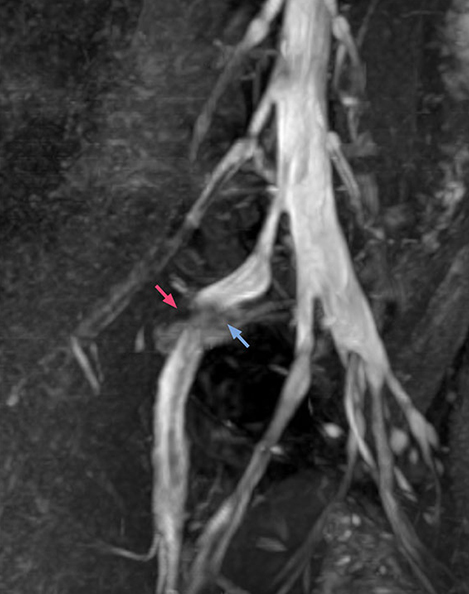

According to Tanji, methods such as ProSet FFE, STIR or 3D VISTA are anatomically nonselective because background signals, for instance from blood vessels, often interfere with nerves, which hampers evaluation of details, especially at the peripheral side of the nerves.

“The intra-luminal signal of veins, especially around the intervertebral space, can be suppressed well with NerveVIEW. As a result, we can easily observe the detailed nerve structure around the posterior ganglion,” he says. “This is why we use 3D NerveVIEW for intraforaminal stenosis and extraforaminal stenosis/herniation (lateral disc herniation). On the other hand, if herniation is suspected to exist inside the dorsal root ganglion (DRG), balanced TFE or ProSet-FFE is applied. NerveVIEW is not suitable for evaluating the median type of herniation.”

“Recently, the two surgical methods extreme and oblique lateral interbody fusion (XLIF and OLIF) have become mainstream for minimally invasive treatment of lumbar spinal canal stenosis and intervertebral foramen stenosis. With these surgical techniques, the spine is approached from the flank, and prior knowledge of the exact anatomy of the lumbosacral plexus would be extremely helpful. To that end, high slice resolution (less than 1 mm acquisition) that enables sharper sagittal MPR images will be needed.”